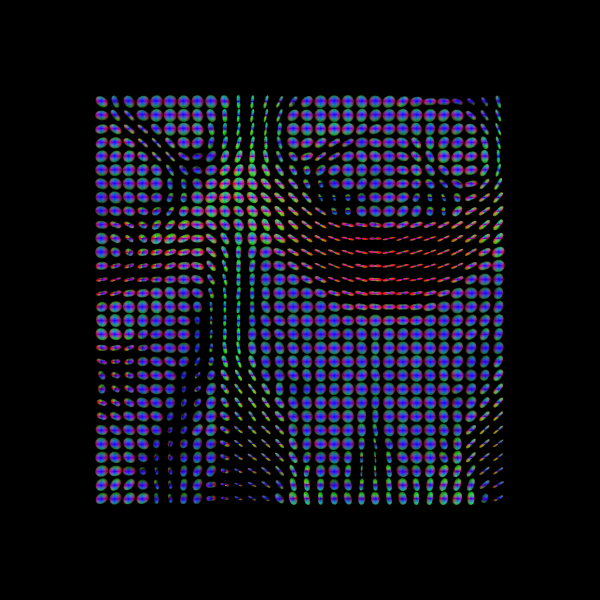

For quality assurance, we can visualize an axial slice from the direction field estimated by the CSA model. Each glyph represents a local fiber orientation derived from the ODF peaks. The underlying ODFs are not shown here.

scene = window.Scene()

scene.add(

actor.peak_slicer(

csa_peaks.peak_dirs[20:50, 55:85, 37:38], peaks_values=csa_peaks.peak_values[20:50, 55:85, 37:38], colors=None

)

window.record(scene=scene, out_path="csa_direction_field.png", size=(600, 600))

Image("csa_direction_field.png")